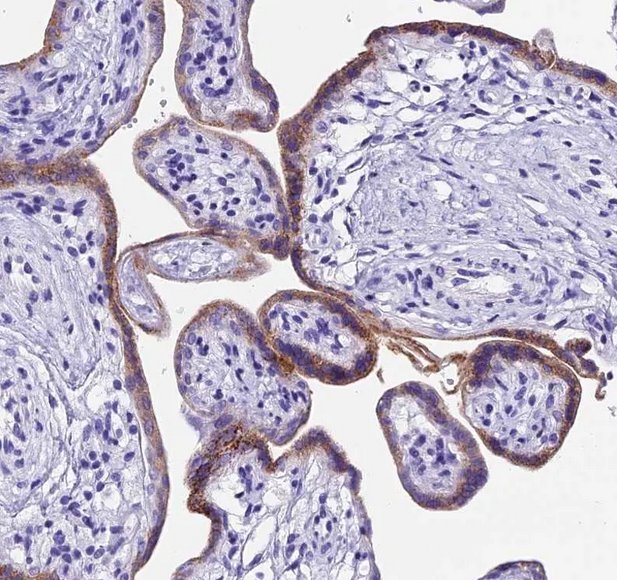

PDL1 Expression by Trophoblastic cells protects from maternal rejection

Human trophoblastic cells display many of the features of malignant cells such as cellular growth and their ability to invade normal tissue including blood vessels and are apparently not eradicated by the host immune system. These trophoblastic cells are genetically significantly different from the mother and should initiate a maternal immune rejection. This is however suppressed thank to the PD1-PDL1 interaction